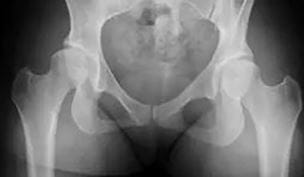

Novel Dual Hip Preservation Technique Grows in International Prominence

Innovations in Orthopaedics | Summer 2024

A Joint Effort

New, collaborative approach to treating young adult hip dysplasia combines two procedures in one surgery - UH Department of Orthopaedics | Winter 2018